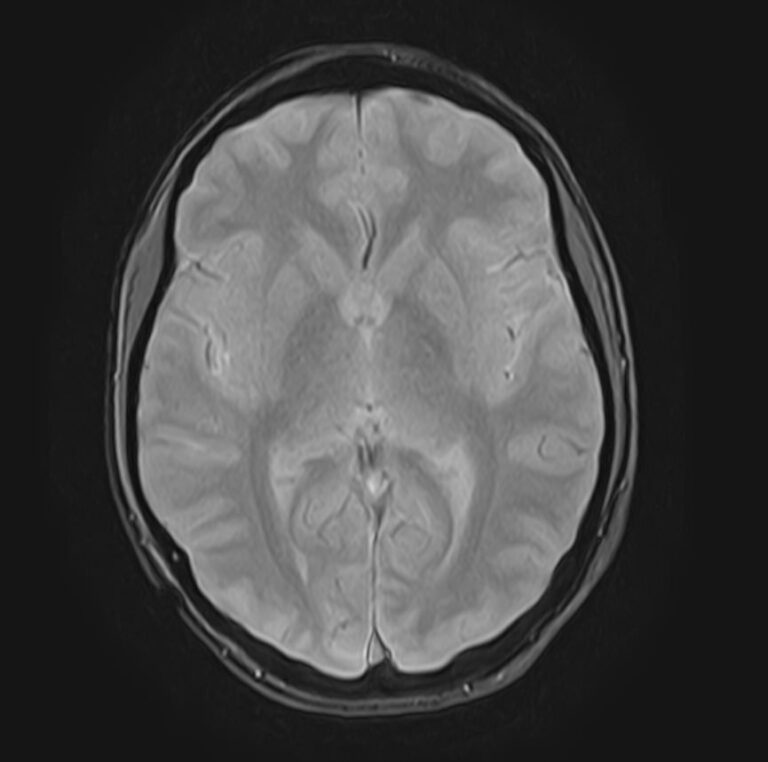

МРТ головного мозга является наиболее информативным, безопасным и доступным методом исследования, который позволяет оценить состояние всех структур и сосудистой системы головного мозга, выявить возможные патологические процессы.

Что показывает МРТ головного мозга

С помощью  магнитно-резонансной томографии можно диагностировать следующие патологии:

• опухолевые образования доброкачественного и злокачественного генеза;

• кистозные образования и псевдокисты;

• очаги ишемического инсульта, кровоизлияния на фоне геморрагического инсульта;

• воспалительные процессы со стороны мозговых оболочек и тканей головного мозга (менингиты, энцефалиты);

• демиелинизирующие заболевания головного мозга, в том числе рассеянный склероз;

• дегенеративные изменения в структурах головного мозга (болезнь Паркинсона, болезнь Альцгеймера, старческая деменция);

• травматические повреждения головного мозга, наличие гематом;

• изменения структуры ткани головного мозга, характерные для эпилепсии;

• патология со стороны сосудов головного мозга (аневризмы, сужение просвета сосудов, сосудистые мальформации).